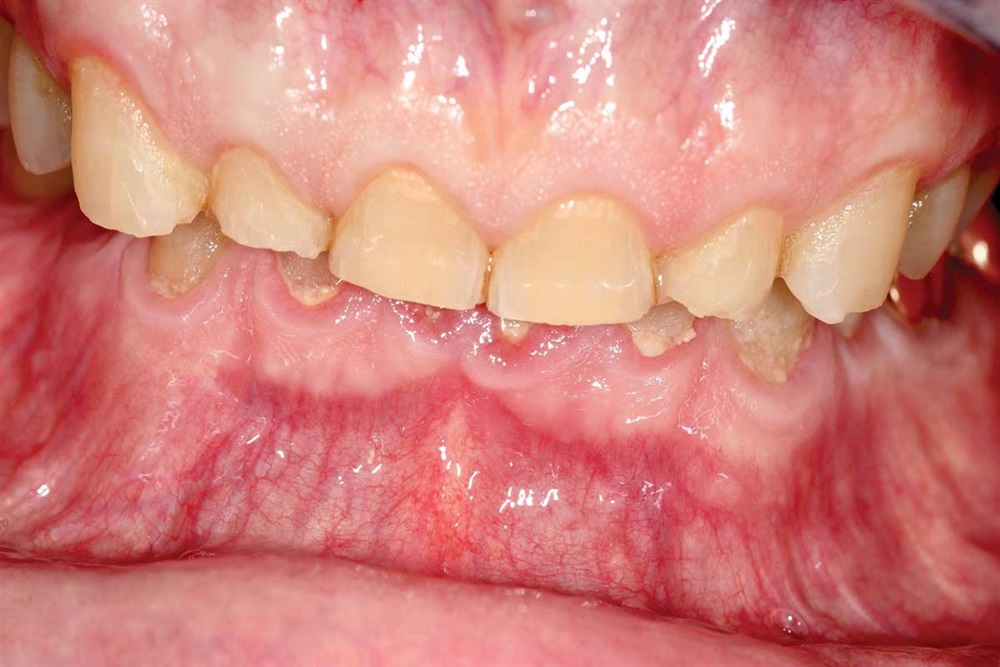

Figs. 22 and 23: Lowers fit palatal to the upper teeth.

Show Your Work

Fig. 23